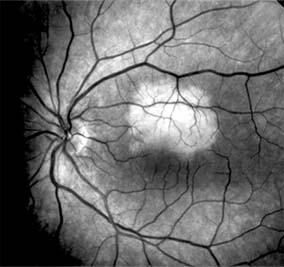

CENTRAL SEROUS CHORIORETINOPATHY

Central serous chorioretinopathy is characterized by serous detachment of the sensory retina as a consequence of focal leakage of fluid from the choriocapillaris through a defect in the retinal pigment epithelium (Figures 10-2 and 10-3). This disease typically affects young to middle-aged men and may be related to life stress events. Most patients present with the sudden onset of blurred vision, micropsia, metamorphopsia, and central scotoma. Visual acuity is often only moderately decreased and may be improved to near-normal with a small hyperopic correction.

Figure 10-2

Figure 10-2: Central serous chorioretinopathy with sensory retinal detachment (arrows) extending into the fovea.

Figure 10-3

Figure 10-3: Fluorescein angiogram of central serous chorioretinopathy shows active disease with both a retinal pigment epithelial detachment (small arrows) and a sensory retinal detachment (large arrows). Two foci of inactive disease (open arrows) are also present.

The diagnosis is made by slitlamp examination of the fundus; the presence of serous detachment of the sensory retina in the absence of ocular inflammation, subretinal neovascularization, an optic pit, or a choroidal tumor is diagnostic. The retinal pigment epithelial lesion appears as a small, round or oval, yellowish-gray spot that is variable in size and may be difficult to detect without the aid of fluorescein angiography. Fluorescein dye leaking from the choriocapillaris may accumulate below the pigment epithelium or sensory retina, resulting in a variety of patterns including the well-recognized smokestack configuration.